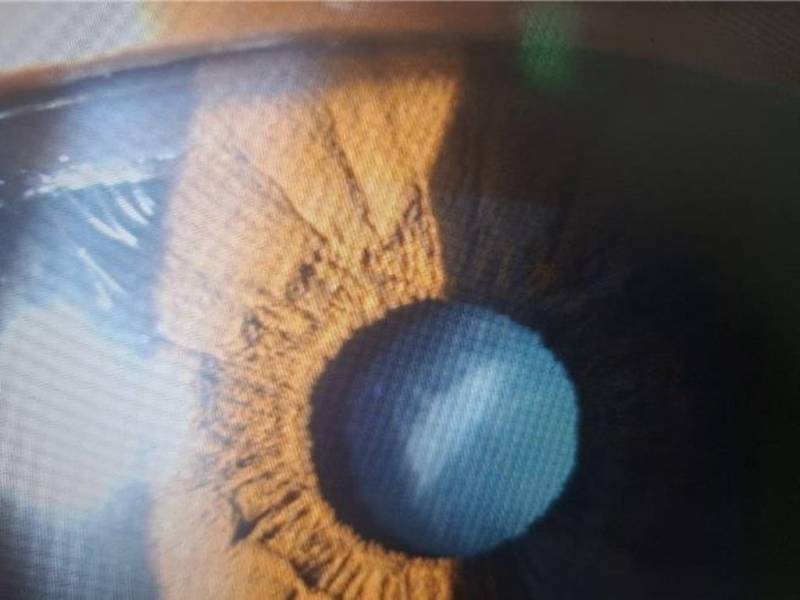

在低倍數的裂隙燈下,可見類似番薯外觀台灣島的白內障。(洪啟庭提供)

洪啟庭表示,在裂隙燈下觀察該病患右眼時,驚覺其白內障混濁位置剛好位於瞳孔中央的前

囊皮質,形態酷似「台灣島」。在低倍數下,病變處呈現類似番薯的外觀;放大倍數後,細

節更是呼之欲出:其長軸傾斜約20度,與台灣中央山脈走向一致;島嶼西海岸在雲嘉一帶微

凸、東海岸相對筆直的弧度也精準對齊。

最令洪啟庭震撼的是,影像左上方與右下方竟能看見一絲絲波濤狀的構造,宛如台灣海峽與

太平洋的浪花。當時正值中華職棒代表隊奪冠,洪啟庭也笑稱這真是「連白內障都Team Tai

wan」 。